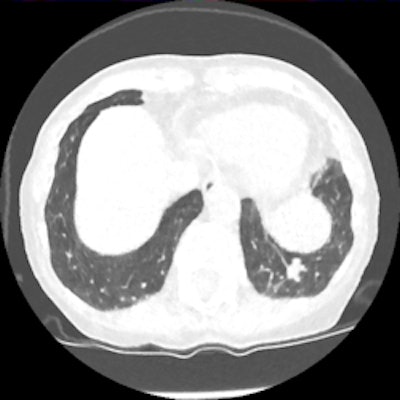

Screening CT of a 74-year-old woman with a 48 pack-year history of smoking. Nodule is seen at ultralow-dose CT (0.2 mSv) using model-based iterative reconstruction (GE Healthcare). Image courtesy of Dr. Ella Kazerooni.